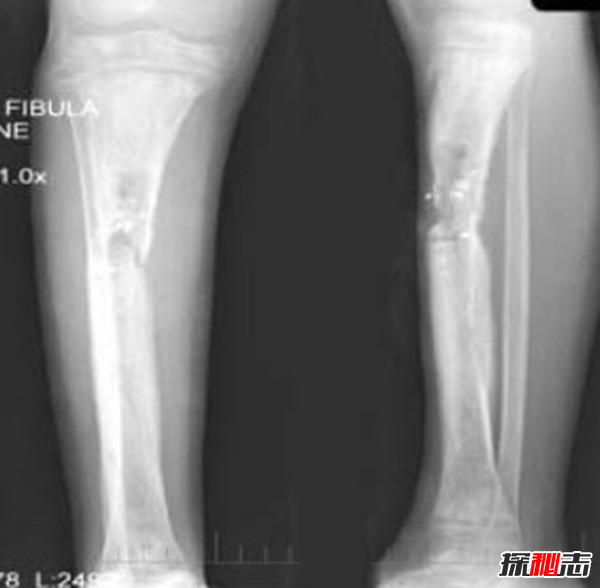

检查:厚皮性骨膜病的X线检查可见胫骨、腓骨、桡骨、尺骨等部位有增生性骨膜炎、弥漫性骨膜增厚。

诊断:根据皮肤及骨骼X线检查见增生性骨膜炎、弥漫性骨膜增厚的典型临床改变可作出诊断。